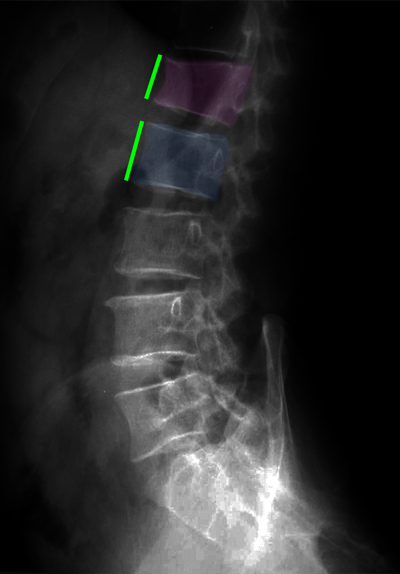

Διαδερμική κυφοπλαστική, ακτινοσκόπηση. Η ειδική βελόνη εισέρχεται διαδερμικά στο σώμα του σπονδύλου (φούξια βέλος) και γίνεται έκπτυξη μπαλονιού το οποίο ανατάσει το οστεοπορωτικό κάταγμα (αριστερά). Κατόπιν πραγματοποιείται έγχυση ακρυλικού πολυμερούς στο σώμα του σπονδύλου για να σταθεροποιηθεί το αναταχθέν κάταγμα (δεξιά). |

Κάταγμα 01 (φούξια) με μείωση του ύψους του σπονδύλου σε σύγκριση με τον υποκείμενο υγιή σπόνδυλο (μπλέ)(αριστερά). Κυφοπλαστική με ανάταξη του κατάγματος και επαναφορά του ύψους του σπονδύλου στο φυσιολογικό (δεξιά). |